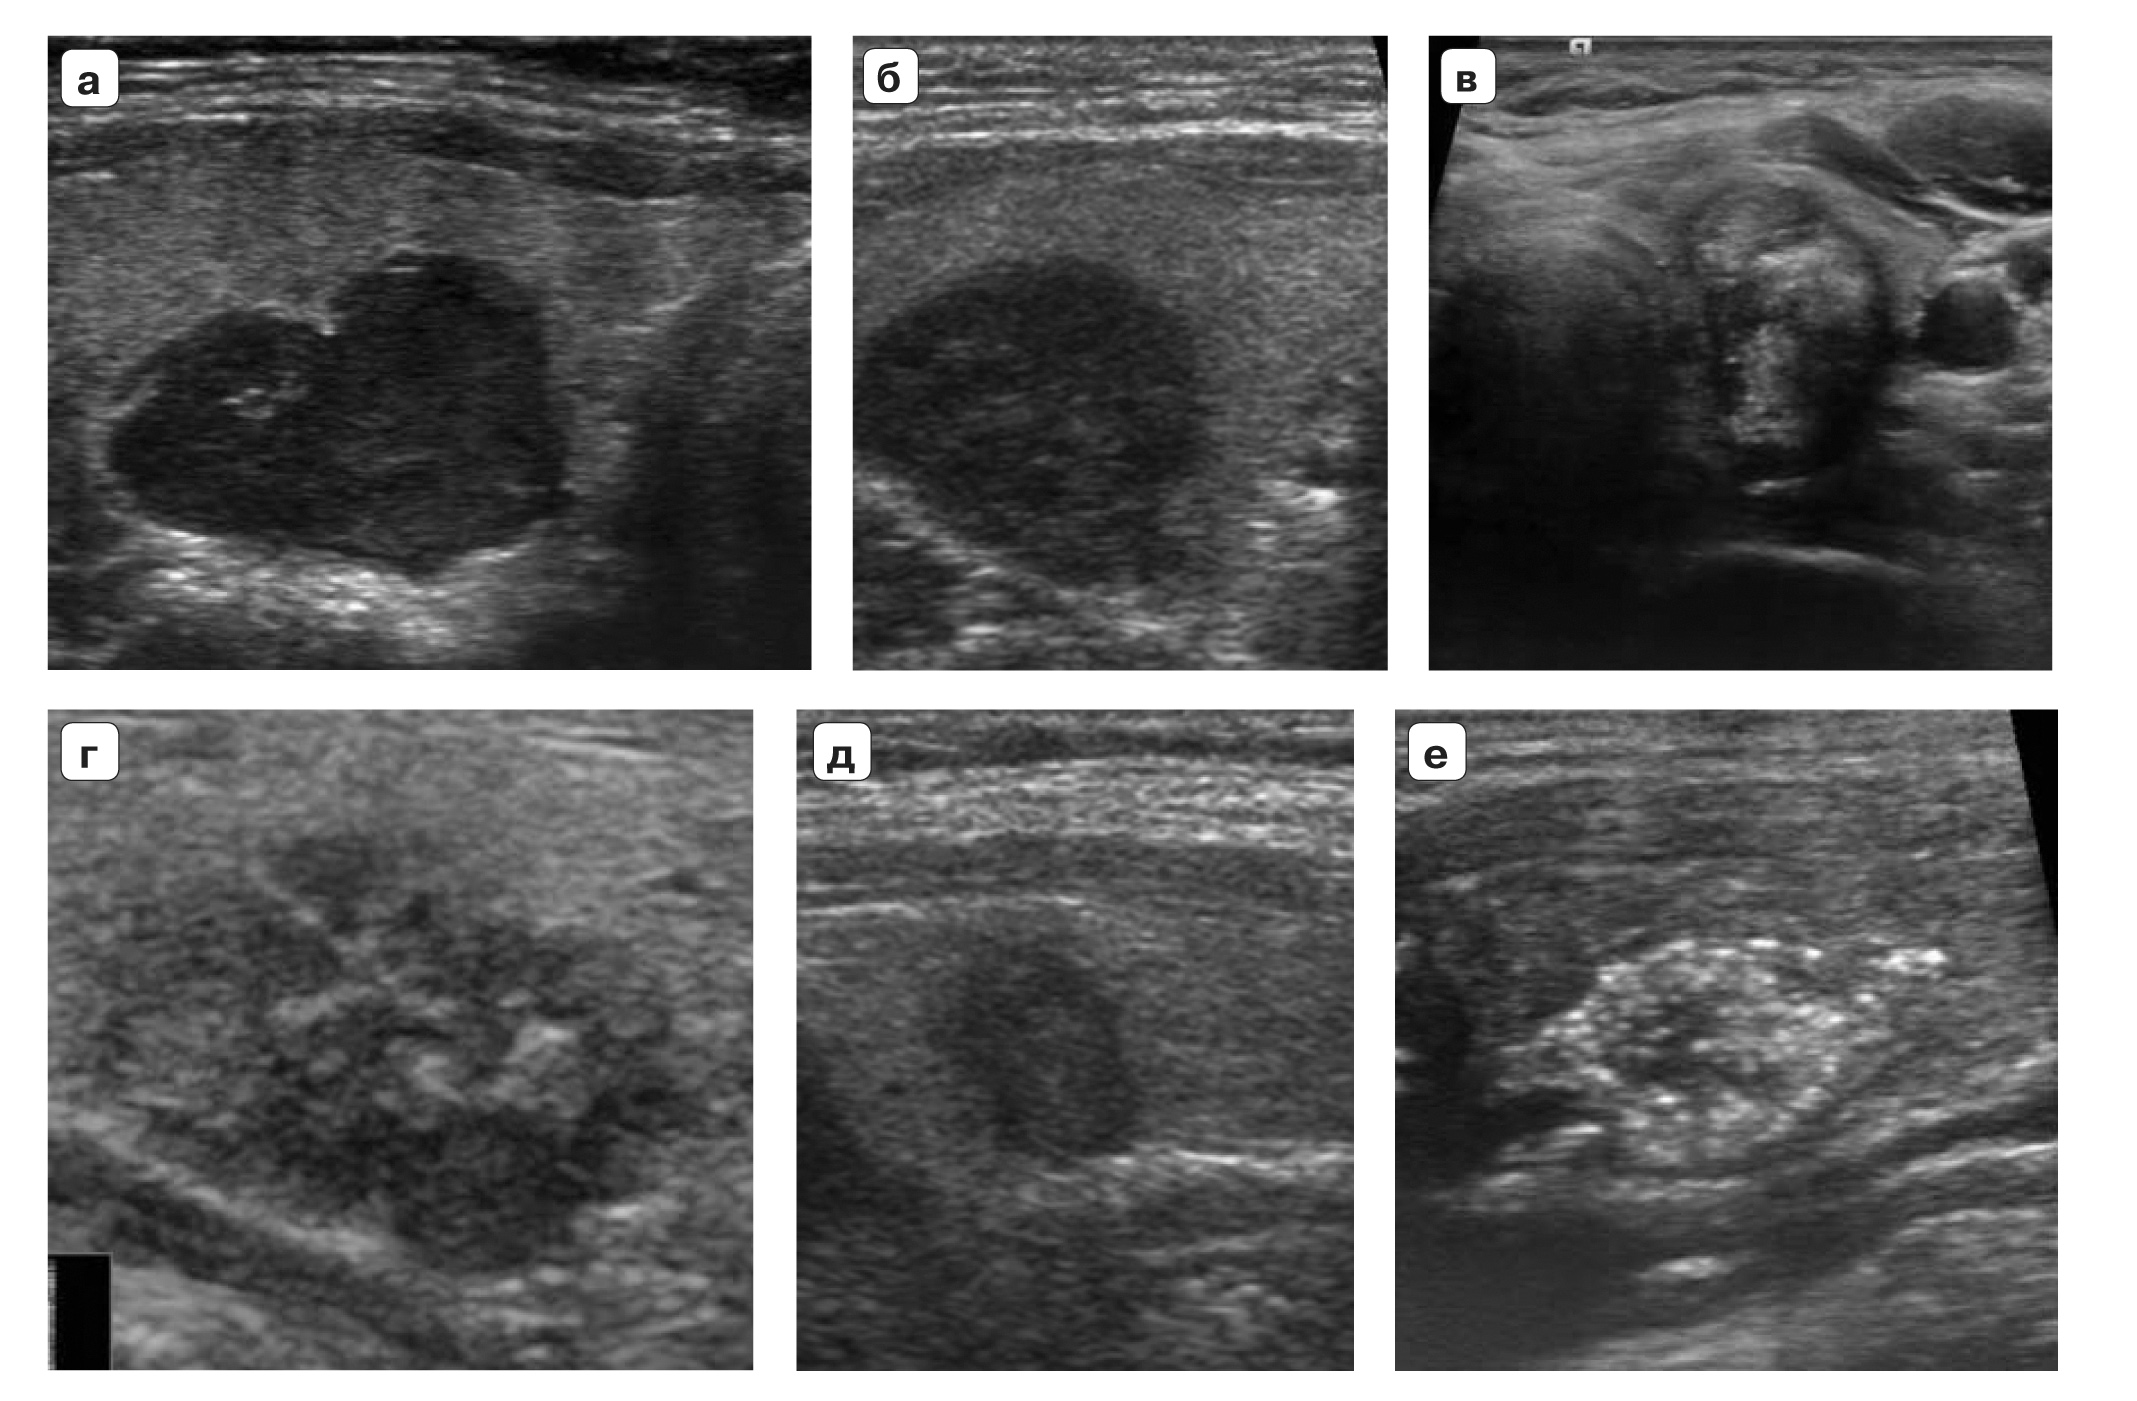

19. Fig. 4. TI-RADS 5. Thyroid nodes> 1.0 cm in size (papillary cancers): a, b - nodes of significantly reduced echogenicity with microcalcifications, with uneven microlobular contours; c - a node of vertical spatial orientation, with fuzzy, uneven contours, significantly reduced echogenicity, with multiple microcalcifications; g - a node with microlobular fuzzy contours, unevenly reduced echogenicity, with microcalcifications; d - a node of significantly reduced echogenicity, vertical spatial orientation, with fuzzy, uneven (radiant) contours; e - a node with fuzzy contours, with multiple microcalcifications.